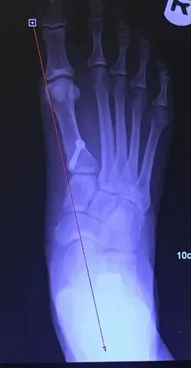

Xrays of Child above (pre and postop)

Pre-operative x-rays of the flatfoot with the talus deviated medially due to subluxing off the calcaneus causing the midtarsal joint to sublux laterally and uncovering of the talar head at the talo-navicular joint (left). The talus bone should line up with or be close to paralletl with a line drawn through the 1st metatarsal shaft (right). This is referred to as Meary's angle.

One case see an improvement in Meary's angle after surgical repair of the flatfoot with a subtalar joint implant which blocks the subluxation of the talus off of the calcaneus.